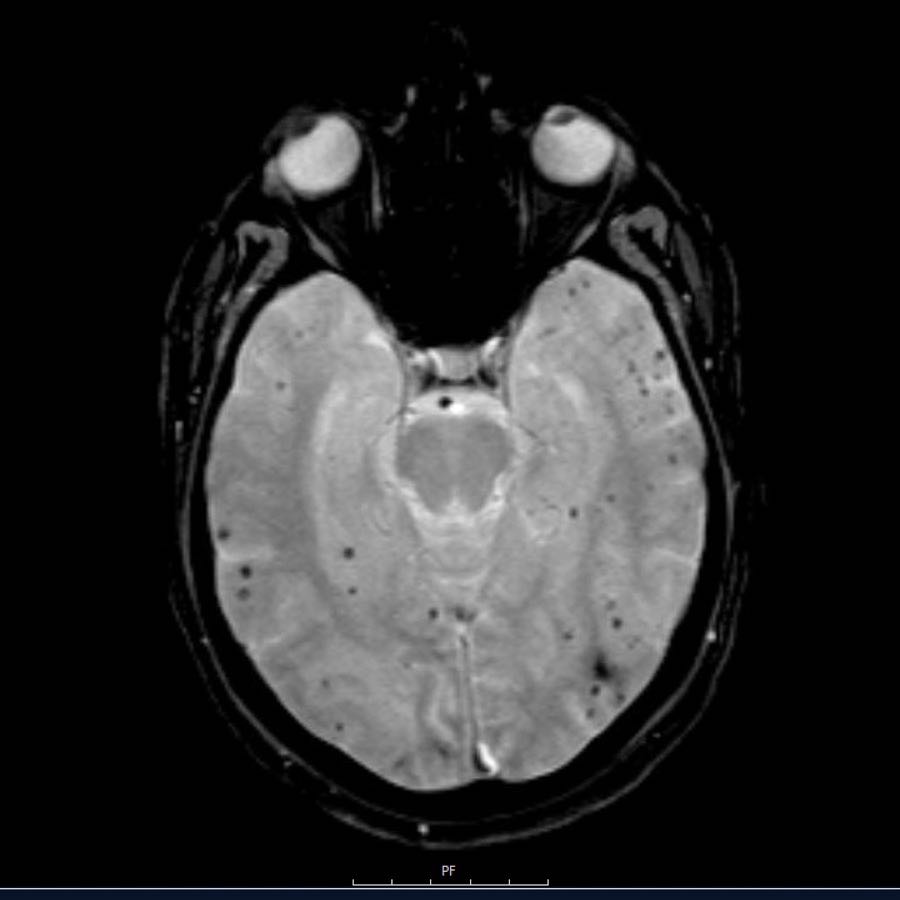

Các ổ xuất huyết nhỏ này còn được gọi là xuất huyết vi thể (microbleeds).

Lưu ý số lượng rất nhiều các ổ xuất huyết nhỏ này, phân bố chủ yếu ở vùng ngoại vi của não.

Bệnh nhân này nhập viện với hình ảnh khối máu tụ tiểu não.

Tiếp tục xem hình ảnh chuỗi xung T1W…

Chuỗi xung T1W cho thấy ổ xuất huyết tăng tín hiệu (mũi tên).

Xuất huyết nội sọ do tăng huyết áp cùng với CAA chiếm 80% nguyên nhân gây khối máu tụ trong nhu mô não.

Cần nghĩ đến CAA khi phát hiện nhiều ổ xuất huyết ngoại vi hoặc xuất huyết thùy ở bệnh nhân cao tuổi.